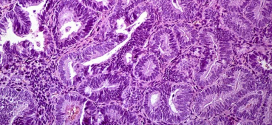

El hepatocarcinoma fibrolamelar. Tumor maligno en general y especialmente el formado por células epiteliales, a saber. Durante los primeros años de vida de una persona, las células normales se dividen más rápidamente para permitir el crecimiento. El cuerpo está compuesto por billones de células vivas. Las células normales del cuerpo crecen, se dividen formando nuevas células y mueren de manera …